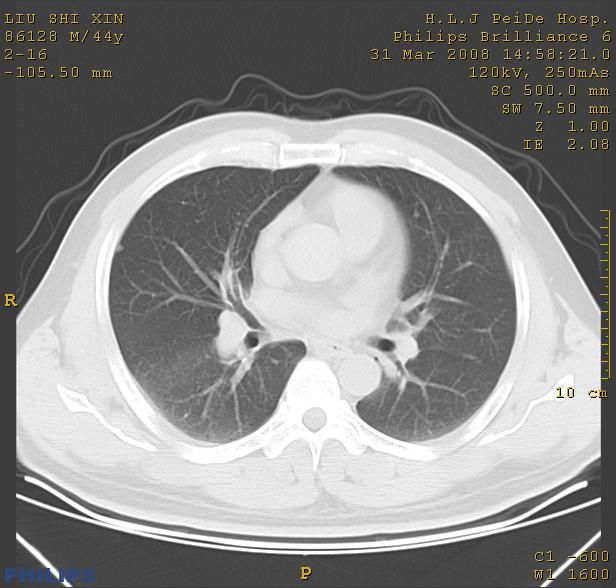

标题: CT13096:请分析胸膜下结节的影像基础是什么 有病理结果 [打印本页]

标题: CT13096:请分析胸膜下结节的影像基础是什么 有病理结果

瘢痕挛缩,胸膜牵拉,血管纠集扭曲,上叶前段支气管显示欠清,周围散在斑片影,以纵隔旁肺癌可能性大。请穿刺检查。

中心型肺癌并阻塞性肺炎及肺内转移

中心型肺癌并阻塞性肺炎、两肺及胸膜多发转移。

结节灶与血管末梢相通象转移灶;小三角状尖部有纤维索是胸膜拉扯征;纵隔旁大片实性影有点状钙化;周围有名显纤维瘢痕征可考虑瘢痕癌

本病例有病理结果是,鳞状上皮癌,胸膜下结节影病现诊断的肿大淋巴结,谢谢大家分析,请问胸膜下结节是肿大淋巴结怎么解释